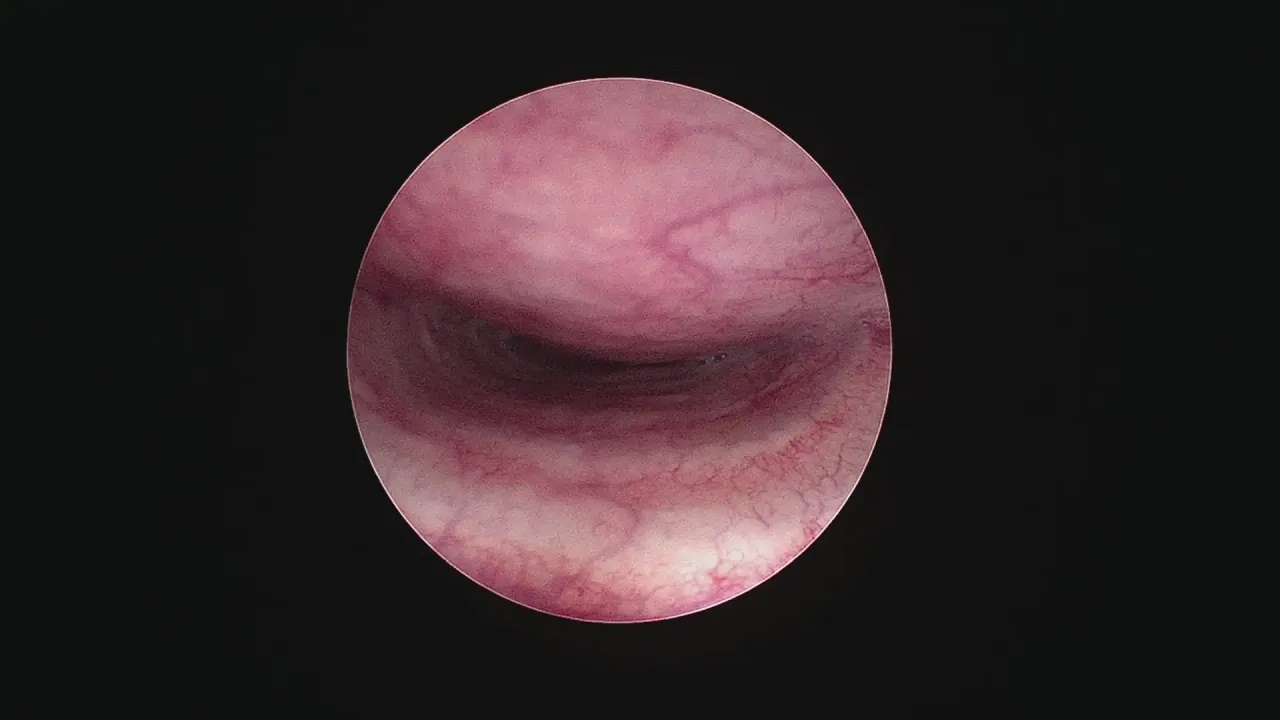

Endoskopia jako "złoty standard": Jak wygląda badanie od środka?

Jeśli RTG nie daje jednoznacznej odpowiedzi lub podejrzewamy zaawansowany przypadek, "złotym standardem" w diagnostyce zapadającej się tchawicy jest endoskopia, czyli tracheoskopia. Jest to badanie inwazyjne, wykonywane w znieczuleniu ogólnym, podczas którego weterynarz wprowadza cienki endoskop z kamerą bezpośrednio do tchawicy psa. Pozwala to na bezpośrednią ocenę wnętrza tchawicy, stanu błony śluzowej, obecności ewentualnych stanów zapalnych oraz, co najważniejsze, na precyzyjne określenie stopnia zapadnięcia się. To badanie daje nam najpełniejszy obraz problemu. Czasem wykonuje się również fluoroskopię, czyli dynamiczne RTG w czasie rzeczywistym, które pokazuje, jak tchawica zachowuje się podczas oddychania.